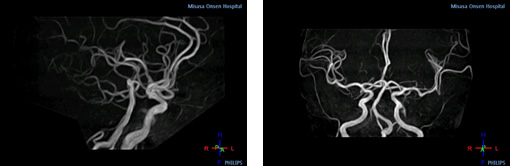

画像例(頭部領域 MRアンギオグラフィー)